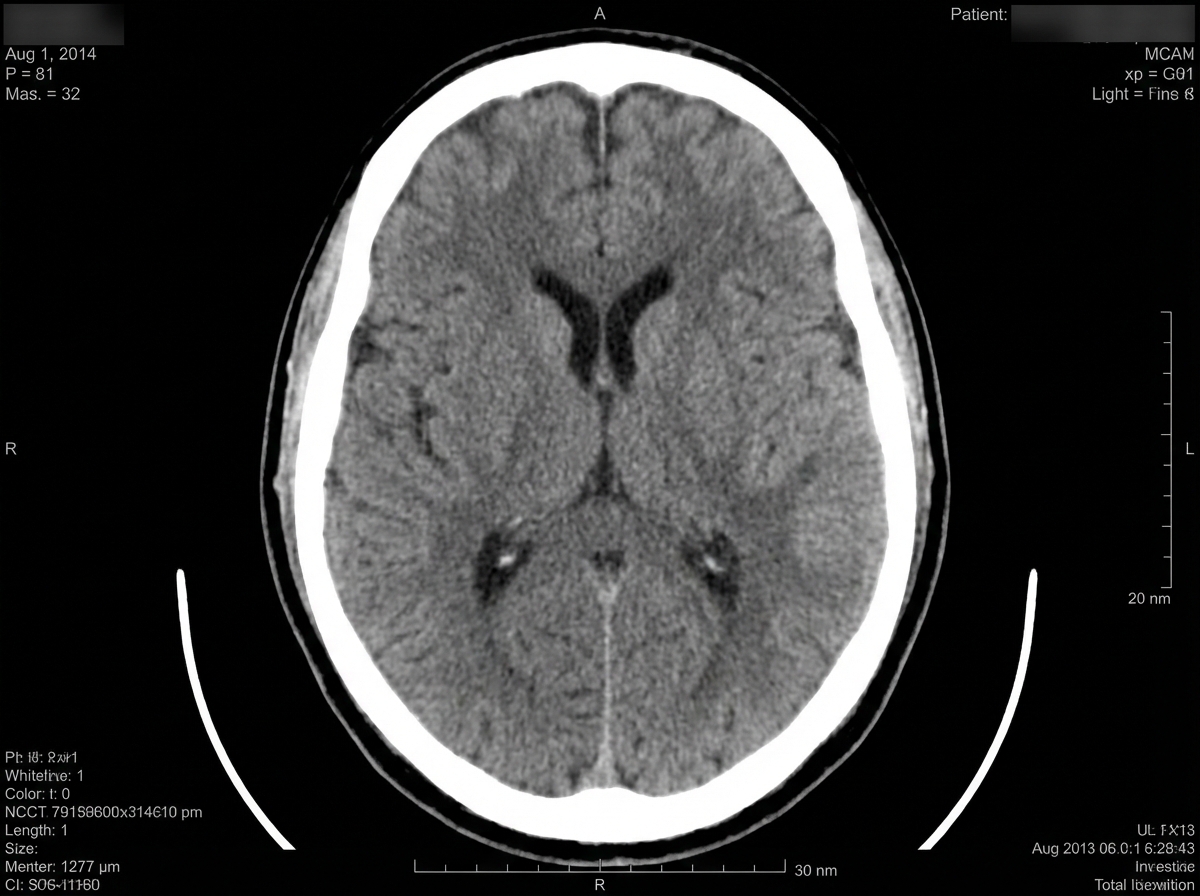

A plain CT scan of the patient's head is performed immediately and shows no evidence of hemorrhage. His temperature is 37.1°C (98.8°F), pulse is 101/min and blood pressure is 174/102 mm Hg. Which of the following is the most appropriate next step in management?

A 74-year-old right-handed woman was referred to the hospital due to concerns of a stroke. In the emergency department, the initial vital signs included blood pressure of 159/98 mm Hg, heart rate of 88/min, and respiratory rate of 20/min. She exhibited paucity of speech and apathy to her condition, although she complied with her physical examination. The initial neurologic evaluation included the following results: Awake, alert, and oriented to person, place, and time No visual field deficits Right-sided gaze deviation with full range of motion with doll’s head maneuver No facial asymmetry Grossly intact hearing No tongue deviation, equal palatal elevation, and good guttural sound production Absent pronator or lower extremity drift Decreased sensation to light touch on the right leg Normal appreciation of light touch, pressure, and pain Normal proprioception and kinesthesia Manual muscle testing: 5+ right and left upper extremities 5+ right hip, thigh, leg, and foot 3+ left hip and thigh 2+ left leg and foot A head computed tomography (CT) scan and a head magnetic resonance imaging (MRI) confirmed areas of ischemia. Which artery is the most likely site of occlusion?